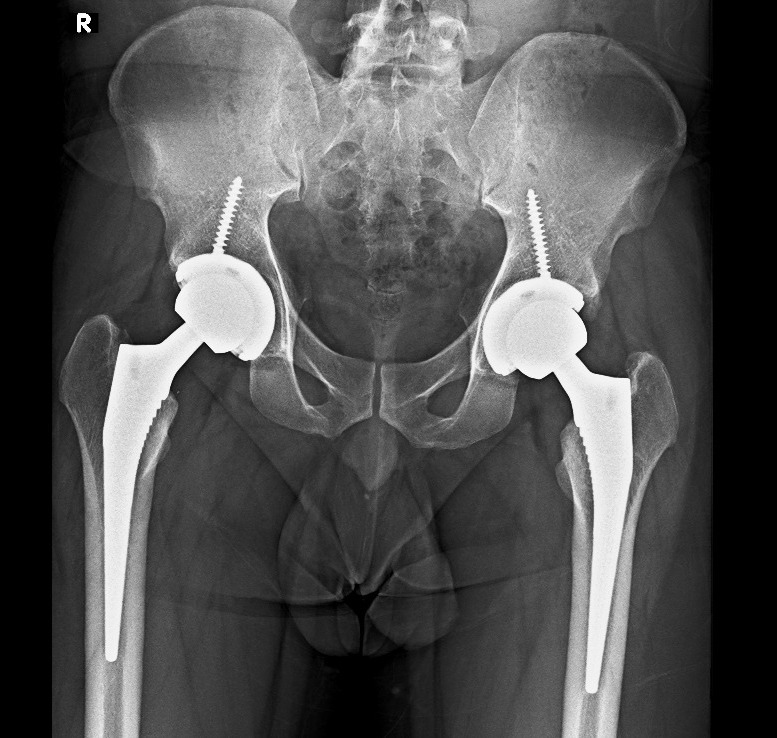

Hip Replacement Surgery: Reclaim Your Stride Without the Grind Woke up dreading stairs because your hip screams with every step? Or maybe gardening, golfing, or just walking the dog feels impossible thanks to arthritis or a bad fall. You're not alone—millions battle hip pain that pills and PT can't fix. Enter hip replacement surgery: a proven fix swapping your worn-out joint for smooth artificial parts, getting 95% of patients back to daily joys pain-free. At Fast Track Knee Replacement—led by expert Dr. Aman Dua—we deliver fast-track hip recoveries tailored for active Indians. Think of your hip as a ball-and-socket marvel: the femur's 'ball' glides in the pelvis socket, cushioned by cartilage. Osteoarthritis, fractures, or avascular necrosis erode that padding, causing bone-on-bone agony, stiffness, and limping. When lifestyle tweaks fail, total hip arthroplasty (THA) steps up. It's gold-standard, with implants lasting 15-25 years. Prep is straightforward: X-rays, bloodwork, and a surgeon chat confirm you're ready (most candidates over 50, but fit younger folks qualify). Dr. Dua favors minimally invasive anterior or posterior approaches—smaller cuts mean less muscle trauma and quicker bounces back. Under general or spinal anesthesia (1-2 hours), the surgeon: Incises over the hip (4-6 inches). Removes damaged head and socket. Fits a titanium stem into the femur, topped with a ceramic/metal ball. Secures a durable plastic/ceramic liner in the reamed socket. Tests motion, closes up. Modern perks? Robotic precision for perfect alignment, reducing wear. Post-op, you're in recovery monitoring vitals, then same-day or next-day discharge for qualifying patients. Recovery's a team sport. Days 1-3: Walk with a walker, pain meds, and ice. By week 2, ditch aids; PT builds strength. Avoid hip-twisting precautions (like crossing legs) for 6 weeks to prevent dislocation (rare, <2%). Full return to driving (4-6 weeks), desk work (2 weeks), or sports (3-6 months). Success? 90-95% report dramatic relief; complications like infection (<1%) or clots are managed proactively. Patient win: Raj, 58, Delhi exec, ditched his cane post-THA: 'Back to morning walks at Lodhi Gardens—no pain!' Outcomes shine with Dr. Dua's protocol: enhanced rehab, blood conservation, and follow-ups. Book Your Path to Pain-Free Hips Today! Consult Dr. Aman Dua at Fortis Escorts Hospital, Okhla Road, Near Sukhdev Vihar Metro Station, Delhi 110025. Call/WhatsApp: +91 87500 05633. Email: cjd.clinic@gmail.com. Clinic: Mon-Sat 9:30 AM–4 PM. Video consults available. Easy Online Booking: www.fasttrackkneereplacement.com—slots fill fast!